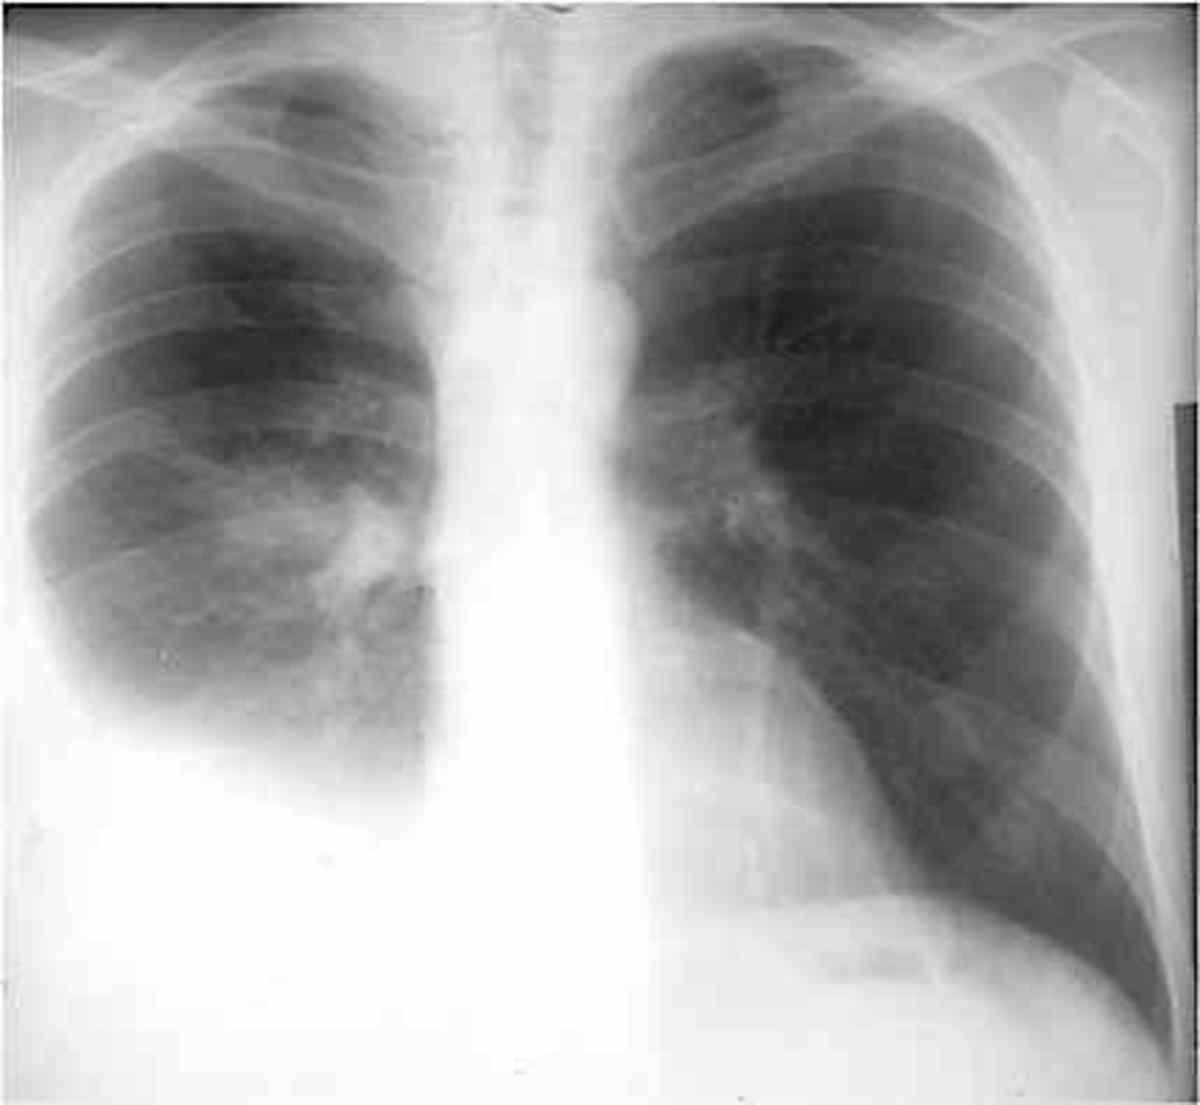

But the basics of chest xray here will guide you through various aspects, including counting ribs, pa vs ap view, inspiratory vs expiratory xray, erect vs supine, lucency and. In consolidation the alveolar spaces become filled with fluid making them appear white, whereas the airways retain air making them appear black. Contrast dye can be injected into your blood vessels.

In consolidation the alveolar spaces become filled with fluid making them appear white, whereas the airways retain air making them appear black. It was observed that color signal may appear within the fluid collection in the pleural space. If simple fluid, then the term hydrothorax may be employed, although this is rarely used (other than in combination terms e.g. This.

Asymmetry of lung density is represented as either abnormal whiteness (increased density), or abnormal blackness (decreased density). If simple fluid, then the term hydrothorax may be employed, although this is rarely used (other than in combination terms e.g. This is because of high. Xray green what is an air pocket in the stomach? Look carefully at the nature of the.

Contrast dye can be injected into your blood vessels (to show the vessels), it can be ingested. Air should only be within bowel loops; Asymmetry of lung density is represented as either abnormal whiteness (increased density), or abnormal blackness (decreased density). Once you have spotted asymmetry, the next step is to decide which side is abnormal. It was observed that.

Asymmetry of lung density is represented as either abnormal whiteness (increased density), or abnormal blackness (decreased density). An example commonly used is the element barium, that is delivered in the compound barium sulfate. It was observed that color signal may appear within the fluid collection in the pleural space. It first appears too complicated to read the chest xrays because.